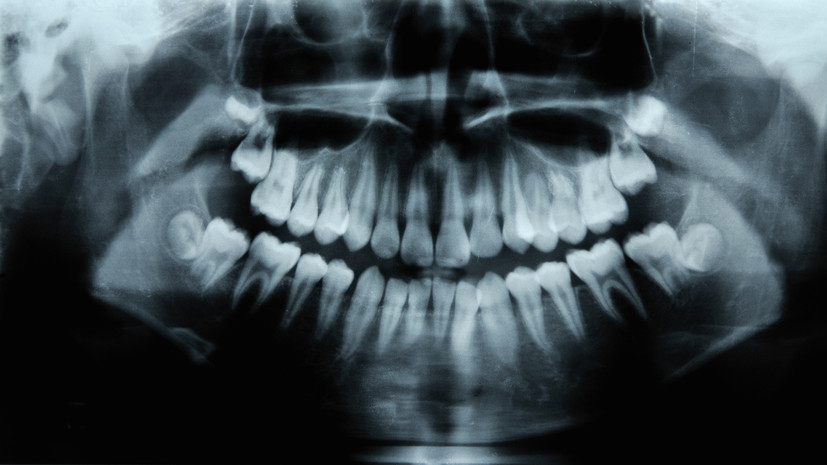

Стоматолог Жук: флюс нельзя игнорировать

В беседе с aif.ru эксперт отметил, что воспаление надкостницы (флюс) является серьёзным заболеванием и требует незамедлительного обращения к врачу.